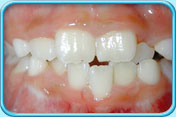

由於恆齒的琺瑯質是稍微透明的,內層黃色的象牙質就透現出來,所以恆齒會呈微黃色。隨年紀漸長,象牙質不斷增厚,牙齒亦會變得比較黃,這情況是正常的。

呈微黃色的恆齒乳齒的琺瑯質不及恆齒的琺瑯質那般透明,因此乳齒呈乳白色。

呈微黃色的乳齒導致牙齒變色的因素有兩種──外在因素和內在因素